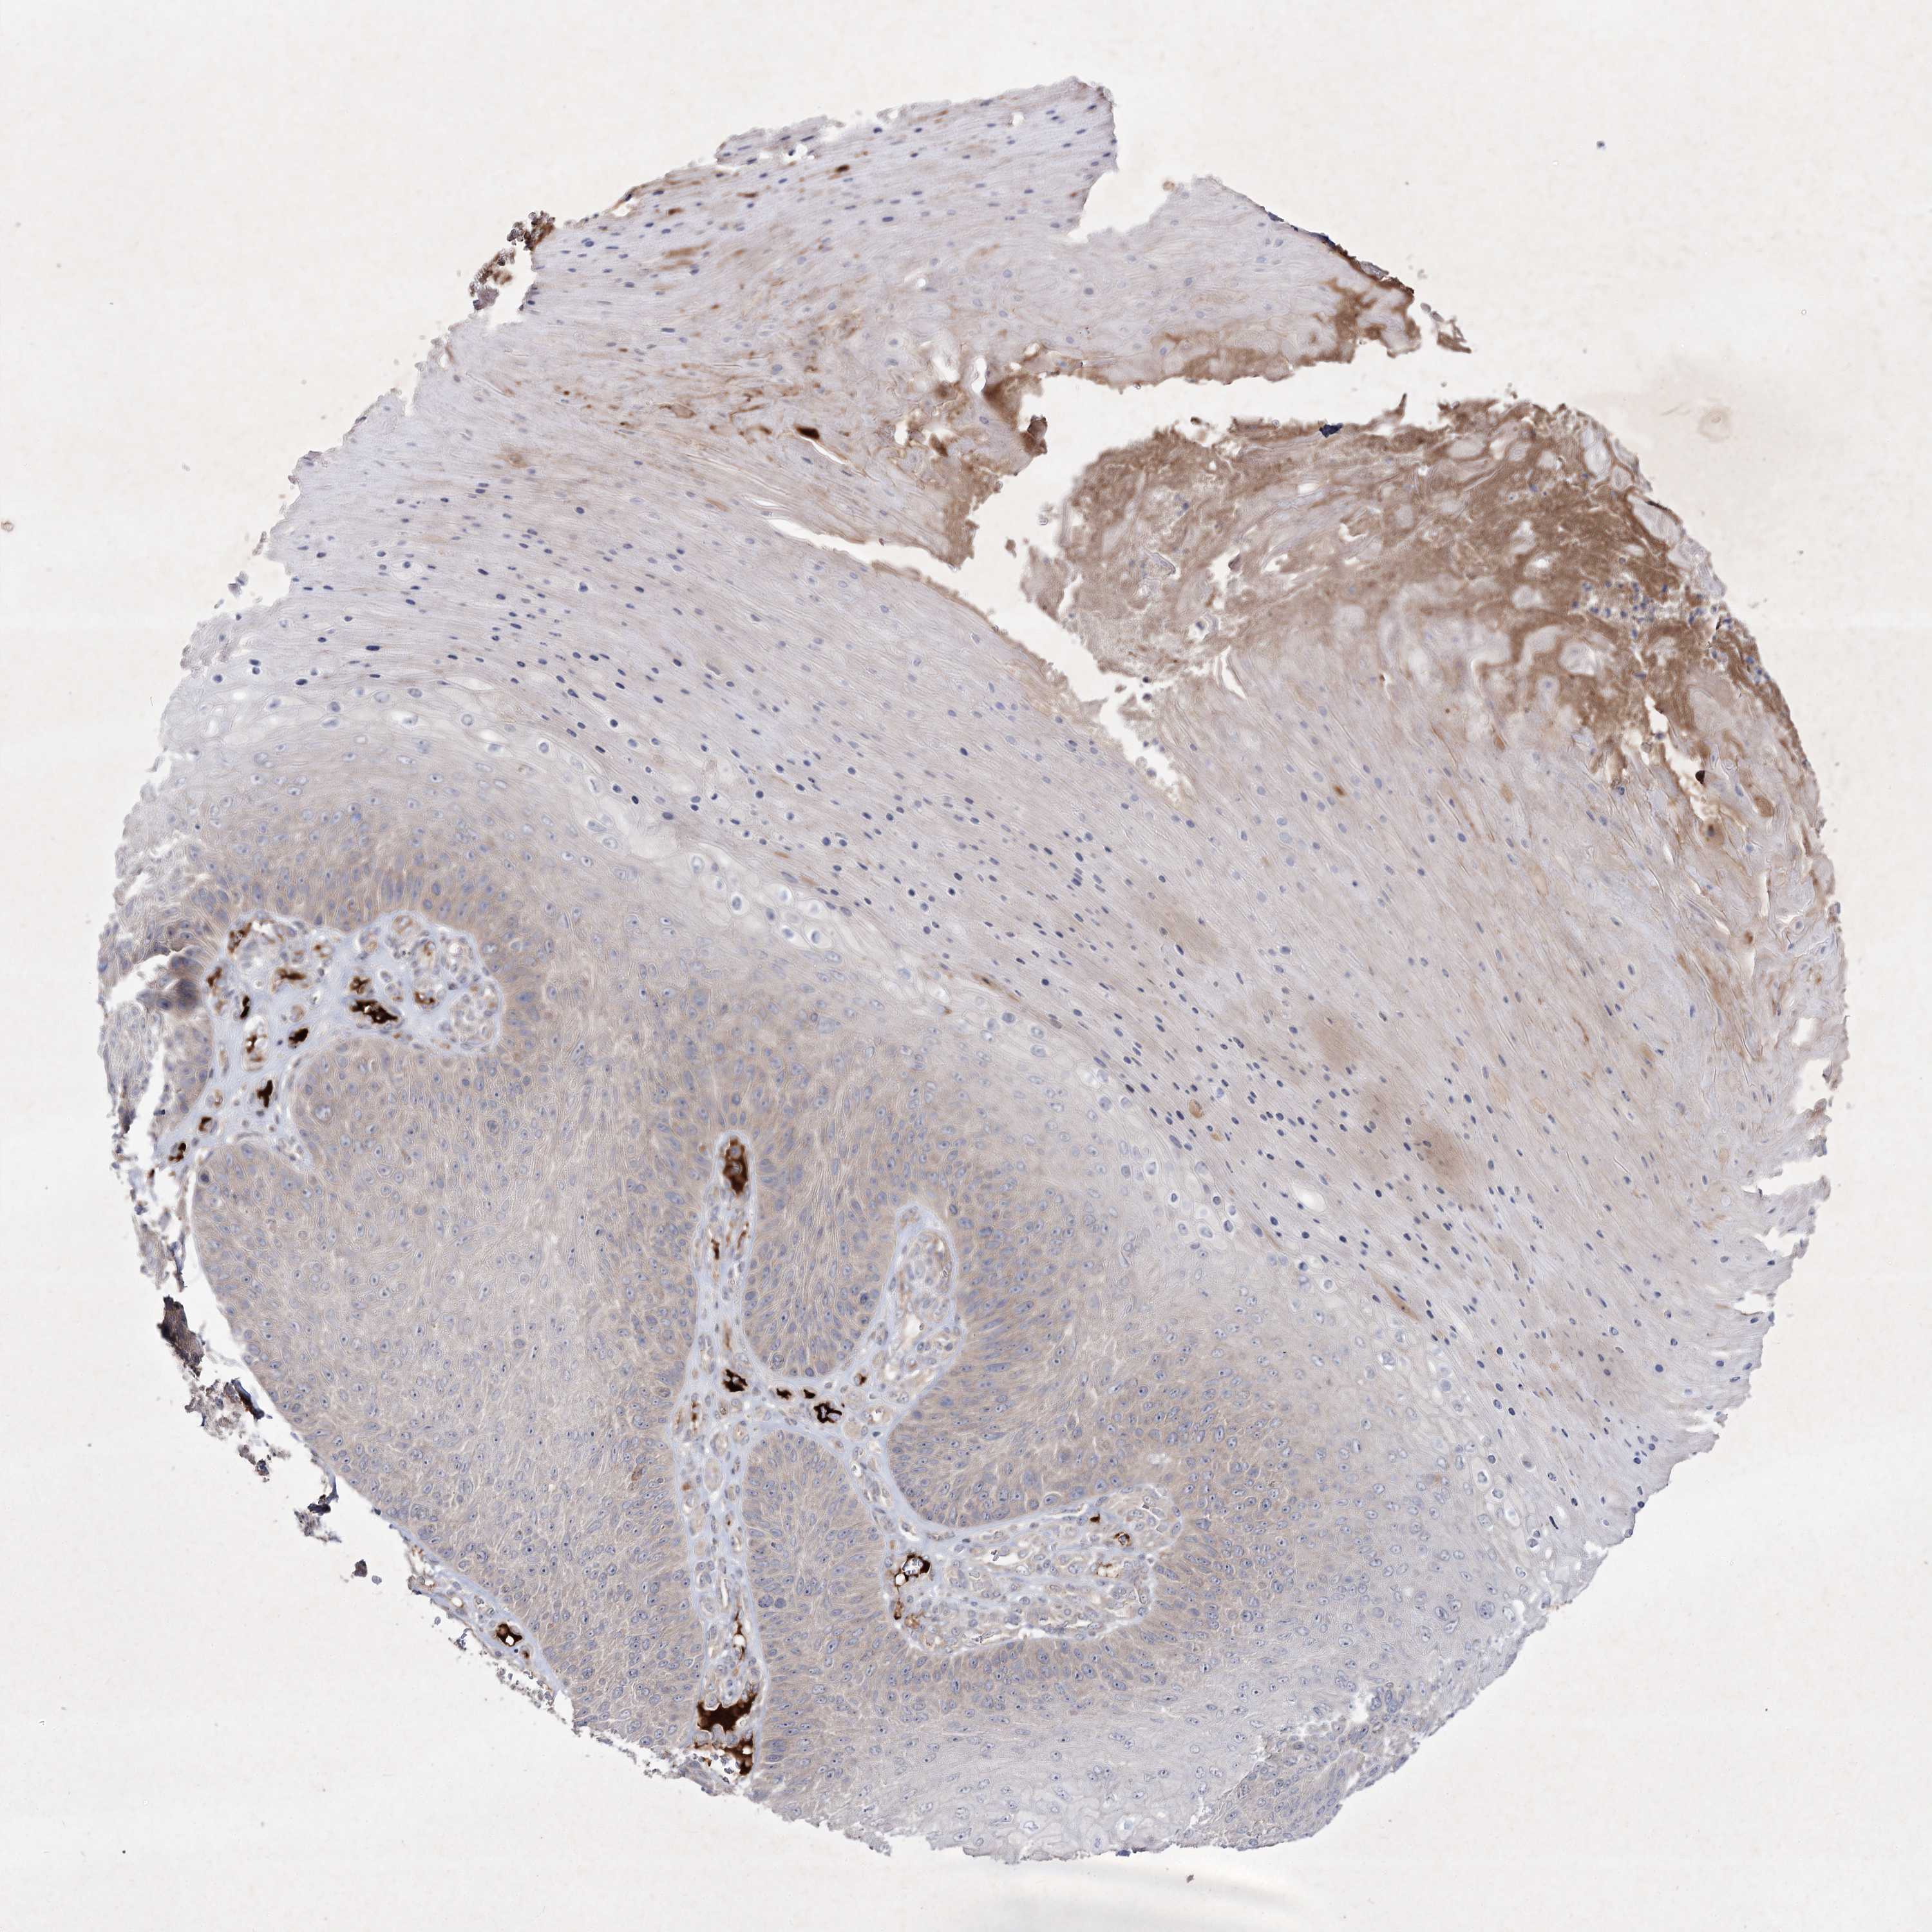

Basal cell and squamous cell cancer

SKIN CANCER - Protein expressioni

A mouse-over function shows sample information and annotation data. Click on an image to view it in a full screen mode. Samples can be filtered based on level of antibody staining by selecting one or several of the following categories: high, medium, low and not detected. The assay and annotation is described here.

Antibody stainingi

Antibody staining in the annotated cell types in the current human tissue is reported as not detected, low, medium, or high, based on conventional immunohistochemistry profiling in selected tissues. This score is based on the combination of the staining intensity and fraction of stained cells.

Each image is clickable and will lead to virtual microscopy that enables deeper exploration of all samples and also displays staining intensity scores, fraction scores and subcellular localization as well as patient and tissue information for each sample.

Antibody HPA036697

Staining

High

Medium

Low

Not detected

Intensity

Strong

Moderate

Weak

Negative

Quantity

>75%

75%-25%

<25%

None

Location

Nuclear

Cytoplasmic/membranous

Cytoplasmic/membranous,nuclear

Squamous cell carcinoma, NOS